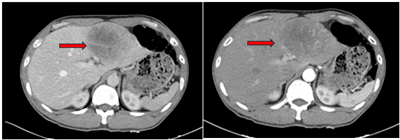

Ca lâm sàng: Điều trị ung thư biểu mô tế bào gan bằng thuốc điều trị đích Sorafenib tại Trung tâm Y học hạt nhân và Ung bướu, Bệnh viện Bạch Mai.

Ngày đăng: 29/01/2026

Ung thư biểu mô tế bào gan (hepatocellular carcinoma –HCC)  là loại ung thư thường gặp đứng thứ hai theo ghi nhận của Tổ chức Globocan Việt Nam năm 2022, ước tính mỗi năm có 24,502 trường hợp bệnh...